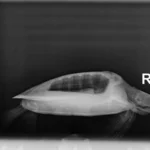

1.85 kg juvenile Atlantic Green sea turtle

Plastron: minor abrasions

In House PCV: 25%, TS: 3.8 , Glucose: 226